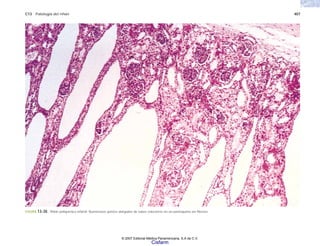

FIGURA 2-21. Atrofia intestinal. a) Vellosidad intestinal normal. b) Vellosidad intestinal atrófica, en caso de sprue.

(b)

(a)